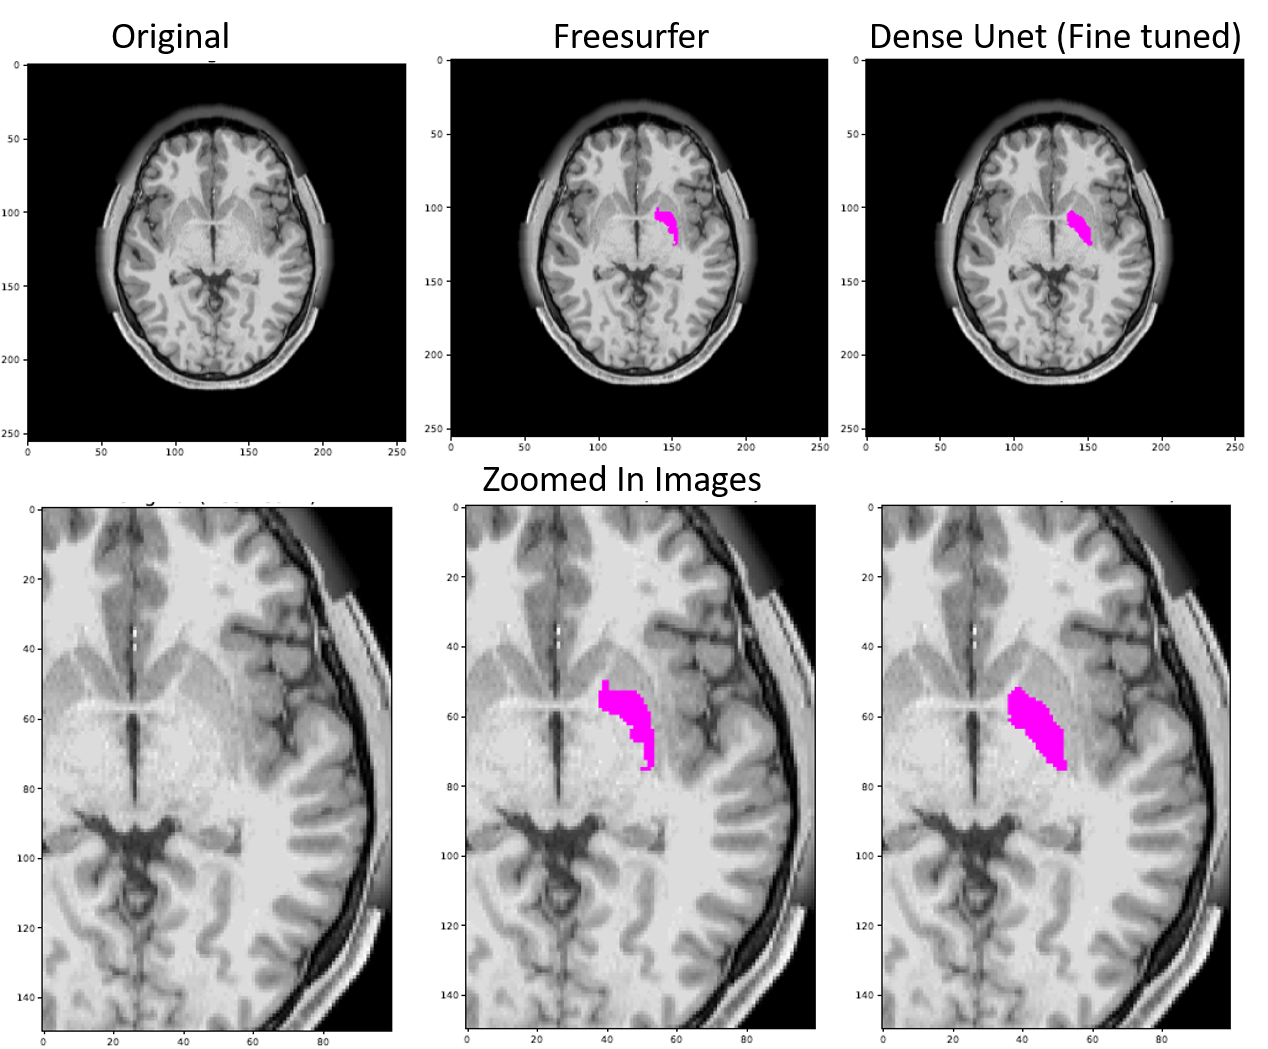

The work of [26] reveals errors in Freesurfer segmentation, thus necessitating manual corrections for quality control. Our reader study results also demonstrates the low quality nature of Freesurfer segmentations and confirms the findings of [26]. As per our readers, the highest difference in the quality of segmentation between the Freesurfer segmentation and Finetuned model segmentation is seen for those regions which showed major boundary errors in the Freesurfer segmentation as demonstrated in figure 5. Those regions are Insula and Pallidum.

In the Freesurfer segmentation, we see boundary errors, inclusion of discontiguous areas, as well as stair-step artifacts along the boundary that render a noisy and non-natural-appearing result. One potential benefit of a deep-learning-based brain segmentation tool over the traditional MRF-based tool is that by training over multiple examples, the model learns that jagged or stair-step boundaries are not consistent, and can not be explained by naturally visible MRI boundaries. The model therefore simply fails to learn the arbitrary jaggedness. For additional examples of Freesurfer vs DenseUNet putamen and pallidum segmentations please refer to figure 16 and figure 17 in the appendix.

Refer to caption

Figure 5: MR image in the axial plane through the level of the insula (left), Freesurfer (FS) (center) and our proposed model, DenseUNet (right) prediction of the insula. It is evident that the FS prediction has errors in both over and underestimation along the boundary, includes discontiguous voxels and is also somewhat non-natural looking with stair-step artifact and a noisy appearance. DenseUNet insula segmentation, on the other hand, obeys well the segment boundaries and lacks the stair-step artifact, rendering a smooth contoured, more natural appearing segmentation.